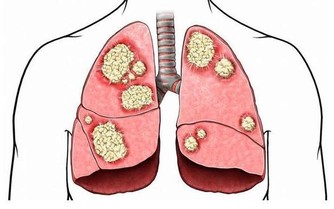

如今,偏愛肉食、無肉不歡的人越來越多,然而紅燒肉、豬蹄湯、糖醋排骨、鵝肝等等這類食物吃得過多,會導致血液中的膽固醇含量漸漸增加。

而且,隨著年齡的增長,人體新陳代謝的速度會有所減慢,這就更加快了膽固醇的積累速度,促使血管快速老化,並影響大腦健康。有研究表明,血液中膽固醇含量較高的人,發生老年癡呆的風險要比普通人高3~5倍。